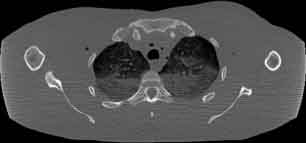

Visible Human male: Sectio transversalis 1342

CT